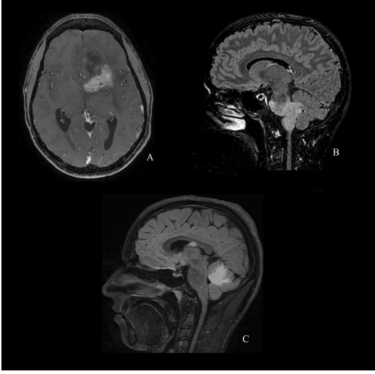

图1. A.40岁男性,左额叶R132G IDH1突变型星形细胞瘤;B.20岁患者,脑干R132G IDH1突变型胶质瘤;C.23岁男性,多中心性R132G IDH1突变型星形细胞瘤,累及松果体和小脑。